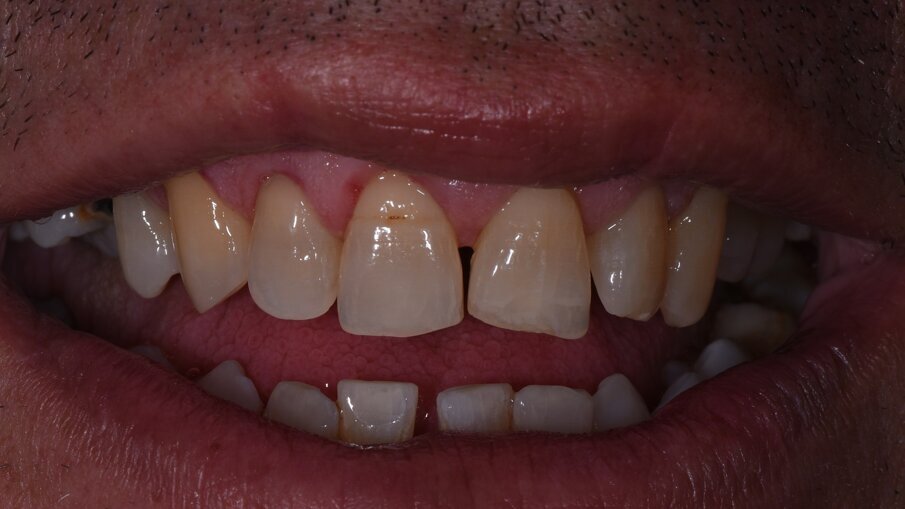

Vengono rilevati gli indici clinici e vengono condivise con il paziente le immagini raccolte con la videocamera intraorale, così da motivarlo di fronte alla presenza di tartaro e infiammazione gengivale e mostrargli le aree critiche. Viene apposto il rilevatore di placca alla fluorescina ed illuminato da una lampada fotopolimeralizzante, che permette di visualizzare la topografia del biofilm batterico (D-BIOTEK-TECNICHE)2, in modo da condividere con il paziente i siti più a rischio del cavo orale (Figg. 1a-2f).

Viene chiesto poi al paziente di provare l’utilizzo dello spazzolino GUM Technique PRO, che grazie alle setole angolate e bi-livello estremamente sottili, permette un efficace controllo del biofilm batterico anche negli spazi interprossimali. Il paziente manifesta la volontà di migliorare l’efficacia della sua routine di igiene orale domiciliare e richiede di provare uno spazzolino elettrico, proprio perché convinto di poter disorganizzare la placca con il maggior tempo a disposizione durante la sera. Effettuiamo una prova con lo spazzolino elettrico GUM PowerCAR ed il paziente dichiara di apprezzare la sensazione di sollievo data dal massaggio gengivale delicato operato dalle setole, anch’esse ultra-sottili (Figg. 3a-3d). Chiediamo al paziente di passare allo spazzolamento interprossimale con lo scovolino in gomma GUM SOFT-PICKS COMFORT FLEX e il paziente rimane favorevolmente colpito dalla facilità di utilizzo di questo strumento, grazie alle setole in gomma morbida che ritiene utili anche per il controllo del food-impaction (Figg. 4a-4f).